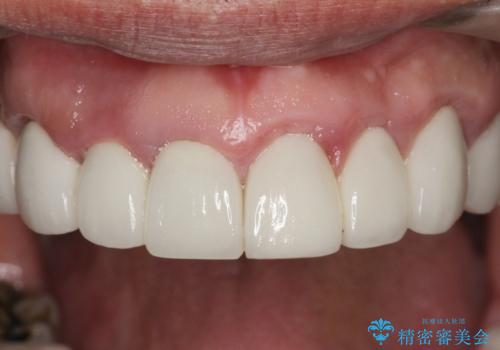

- 前医で行った前歯セラミック形態の改善、常に腫れぼったく歯ブラシの際に出血のある前歯部の治療を希望され来院されました。

前医により、前歯は歯ぐきの奥深くまで形成されこのままの状態でセラミックをやりかえたとしても歯ぐきの腫れの改善は難しい状況です。

歯周外科を行い歯と歯槽骨・歯肉の関係を是正することで歯ぐきの状態を改善し、将来に亘り安定した歯周環境の維持を期待できるセラミック治療を実践します。